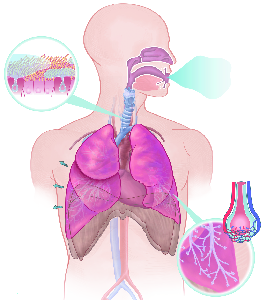

Über 860 Stichworte mit 120 Illustrationen auf 400 Seiten machen aus dem Lexikon der Lunge ein

wertvolles Werk.

Detailreiche Fotografien aus der medizinischen Praxis ergänzen die Texte; moderne, genaue,

wissenschaftliche Zeichnungen geben Einblick in die Anatomie und die Funktion der Lunge und

anderer Organe.